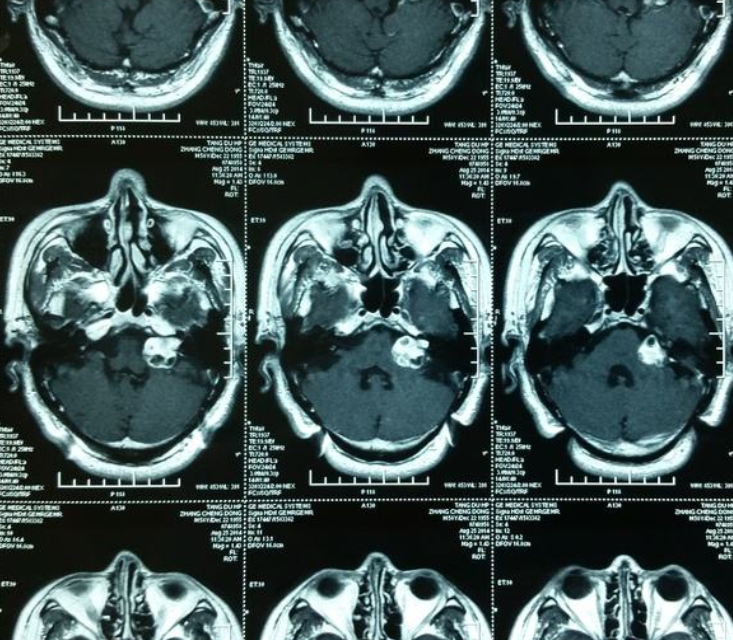

听神经瘤多大需手术?听神经瘤是常见的颅内良性肿瘤,约占颅内良性肿瘤的10%。听神经瘤的体征和症状通常很微妙,可能需要很多年才能发展,较终随着肿瘤的增长,会不断造成听力的损失。

一般听神经瘤的优选治疗方式是手术切除,高手术切除率下的听神经瘤患者一般预后良好,那么,听神经瘤多大需手术?根据病人的病情的不同,肿瘤的大小,症状的不同,来进行个体化的规划。根据现在国际卫生组织(WHO)及相关文献,听神经瘤一般分为四级: